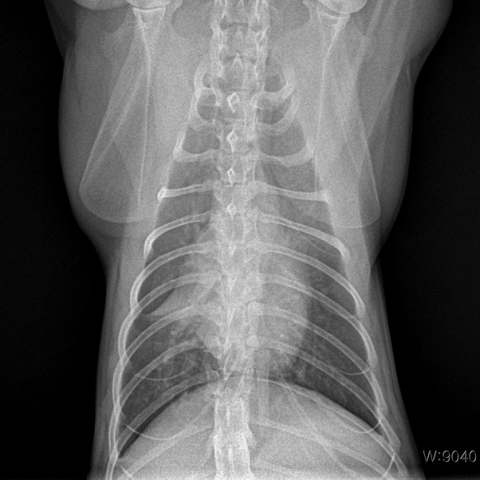

°¡º¿î Áõ»óÀÇ °æ¿ì Áõ»óÀ» ¿ÏÈÇÒ ÀÖ´Â ¾à¹° Ä¡·á¸¦ ¿ì¼±Çϰí, Áõ»óÀÌ Àß ³´Áö ¾Ê°Å³ª ½É°¢ÇÒ °æ¿ì¿¡´Â ¿øÀÎ °¨º°À» À§ÇØ ¹æ»ç¼±, È£Èí±â PCR °Ë»ç, ±â°ü¼¼Ã´ °Ë»ç µîÀ» ÇØº¼ ¼ö ÀÖ½À´Ï´Ù.

±âº»ÀûÀ¸·Î ¿µ»ó °Ë»ç(¹æ»ç¼± °Ë»ç, ÃÊÀ½ÆÄ °Ë»ç)¿Í ¿ä°Ë»ç·Î ¹æ±¤ÀÇ Æó»ö ¿©ºÎ, ¿°Áõ, °á¼®, ¼¼±Õ °¨¿° ¿©ºÎ¸¦ ÆÇ´ÜÇϰí, ³ë·ÉÀ̰ųª Áõ»óÀÌ ½ÉÇÒ °æ¿ì ½ÅÀå ¼öÄ¡¿Í ÀüÇØÁú ¼öÄ¡ µîÀ» üũÇϱâ À§ÇÑ Ç÷¾×°Ë»ç°¡ ÇÊ¿äÇÒ ¼ö ÀÖ½À´Ï´Ù.

°í¾çÀÌÀü¿°¼ºº¹¸·¿°Àº °í¾çÀÌÄڷγª¹ÙÀÌ·¯½º°¡ ¿øÀÎü·Î, °í¾çÀÌ Ã¼³»¿¡ Àẹ »óÅ¿´´ø Äڷγª¹ÙÀÌ·¯½º°¡ ¸Íµ¶¼ºÀ» °¡Áø ¹ÙÀÌ·¯½º·Î º¯À̵Ǿî Àü½Å Àå±â¿¡ ¿°ÁõÀ» ÀÏÀ¸Å°°í, ºóÇ÷, Ȳ´Þ, Èä¼ö, º¹¼ö, ½Å°æ Áõ»óÀ» ÀÏÀ¸Å°´Â Àü¿°¼º ÁúȯÀÔ´Ï´Ù. Àü¿°¼ºº¹¸·¿°Àº ÀÓ»ó Áõ»ó, Ç÷¾× °Ë»ç, Èä/º¹¼ö PCR °Ë»ç, ¹æ»ç¼±, ÃÊÀ½ÆÄ, CT¸¦ ºñ·ÔÇÑ ¿µ»ó °Ë»ç °á°ú¸¦ Á¾ÇÕÀûÀ¸·Î ÆÇ´ÜÇÏ¿© Áø´ÜÇÏ°Ô µË´Ï´Ù. ÀÏ´Ü È®ÁøÀÌ µÇ¸é Ç×¹ÙÀÌ·¯½ºÁ¦¸¦ Åõ¿©ÇÏ´Â °Í¸¸ÀÌ À¯ÀÏÇÑ Ä¡·á ¹æ¹ýÀÔ´Ï´Ù.